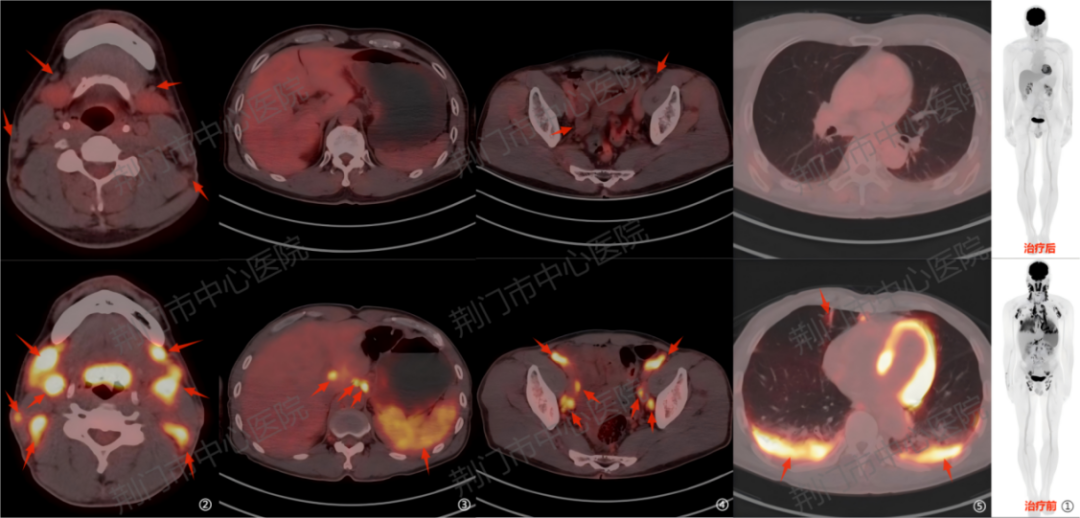

病例二:血管免疫母细胞性 T 细胞淋巴瘤患者治疗结束后 1 个月进行疗效评估。PET/CT 显示多发淋巴结体积及数量减少、代谢明显减低,双肺、胸膜及脾脏病灶代谢显著下降,提示治疗后病灶活性受到有效抑制。